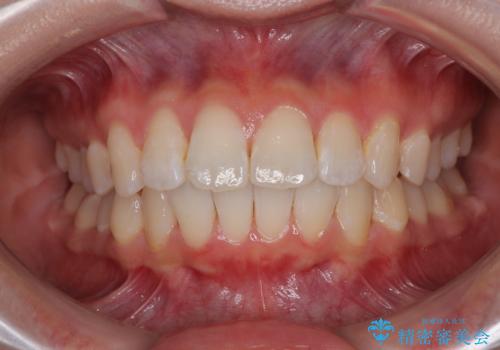

骨格性のディープバイト 補助装置を併用したワイヤー矯正治療で咬み合わせを改善